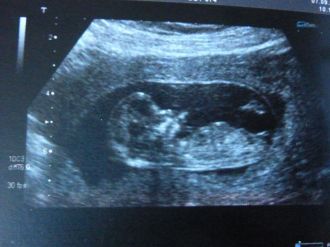

Ca y est nous sommes le 7 septembre 2011, on est dans la salle d'attente, Lona est avec nous, je stresse j'ai peur que quelque chose n'aille pas, le doc nous recoit, malheureusement Lona ne peut pas rentrer avec nous decu elle repart nous attendre en salle d'attente, je m'allonge, elle pose l'appareil sur moi et la soulagement on voit un petit bébé en pleine forme, apparamment tout va bien.

Je suis a 11SA+6 jours.

LCC : 57.2 mm

BIP : 19 mm

DAT : 16 mm

Fémur : 4.5 mm

Epaisseur clarté nucale : 1.1 mm

Je suis rassurée tout va bien ouf, je lui demande si c'est trop tot pour savoir le sexe elle me répond : pour moi c'est une fille a 80 %, vu que le tubercule (qu'on voit sur l'echo) est plutot droit mais a confirmer à la prochaine écho, je suis heureuse, je pleure c'est magique, le futur papa aurai préféré un garcon mais ne desespere pas il attend la confirmation lol